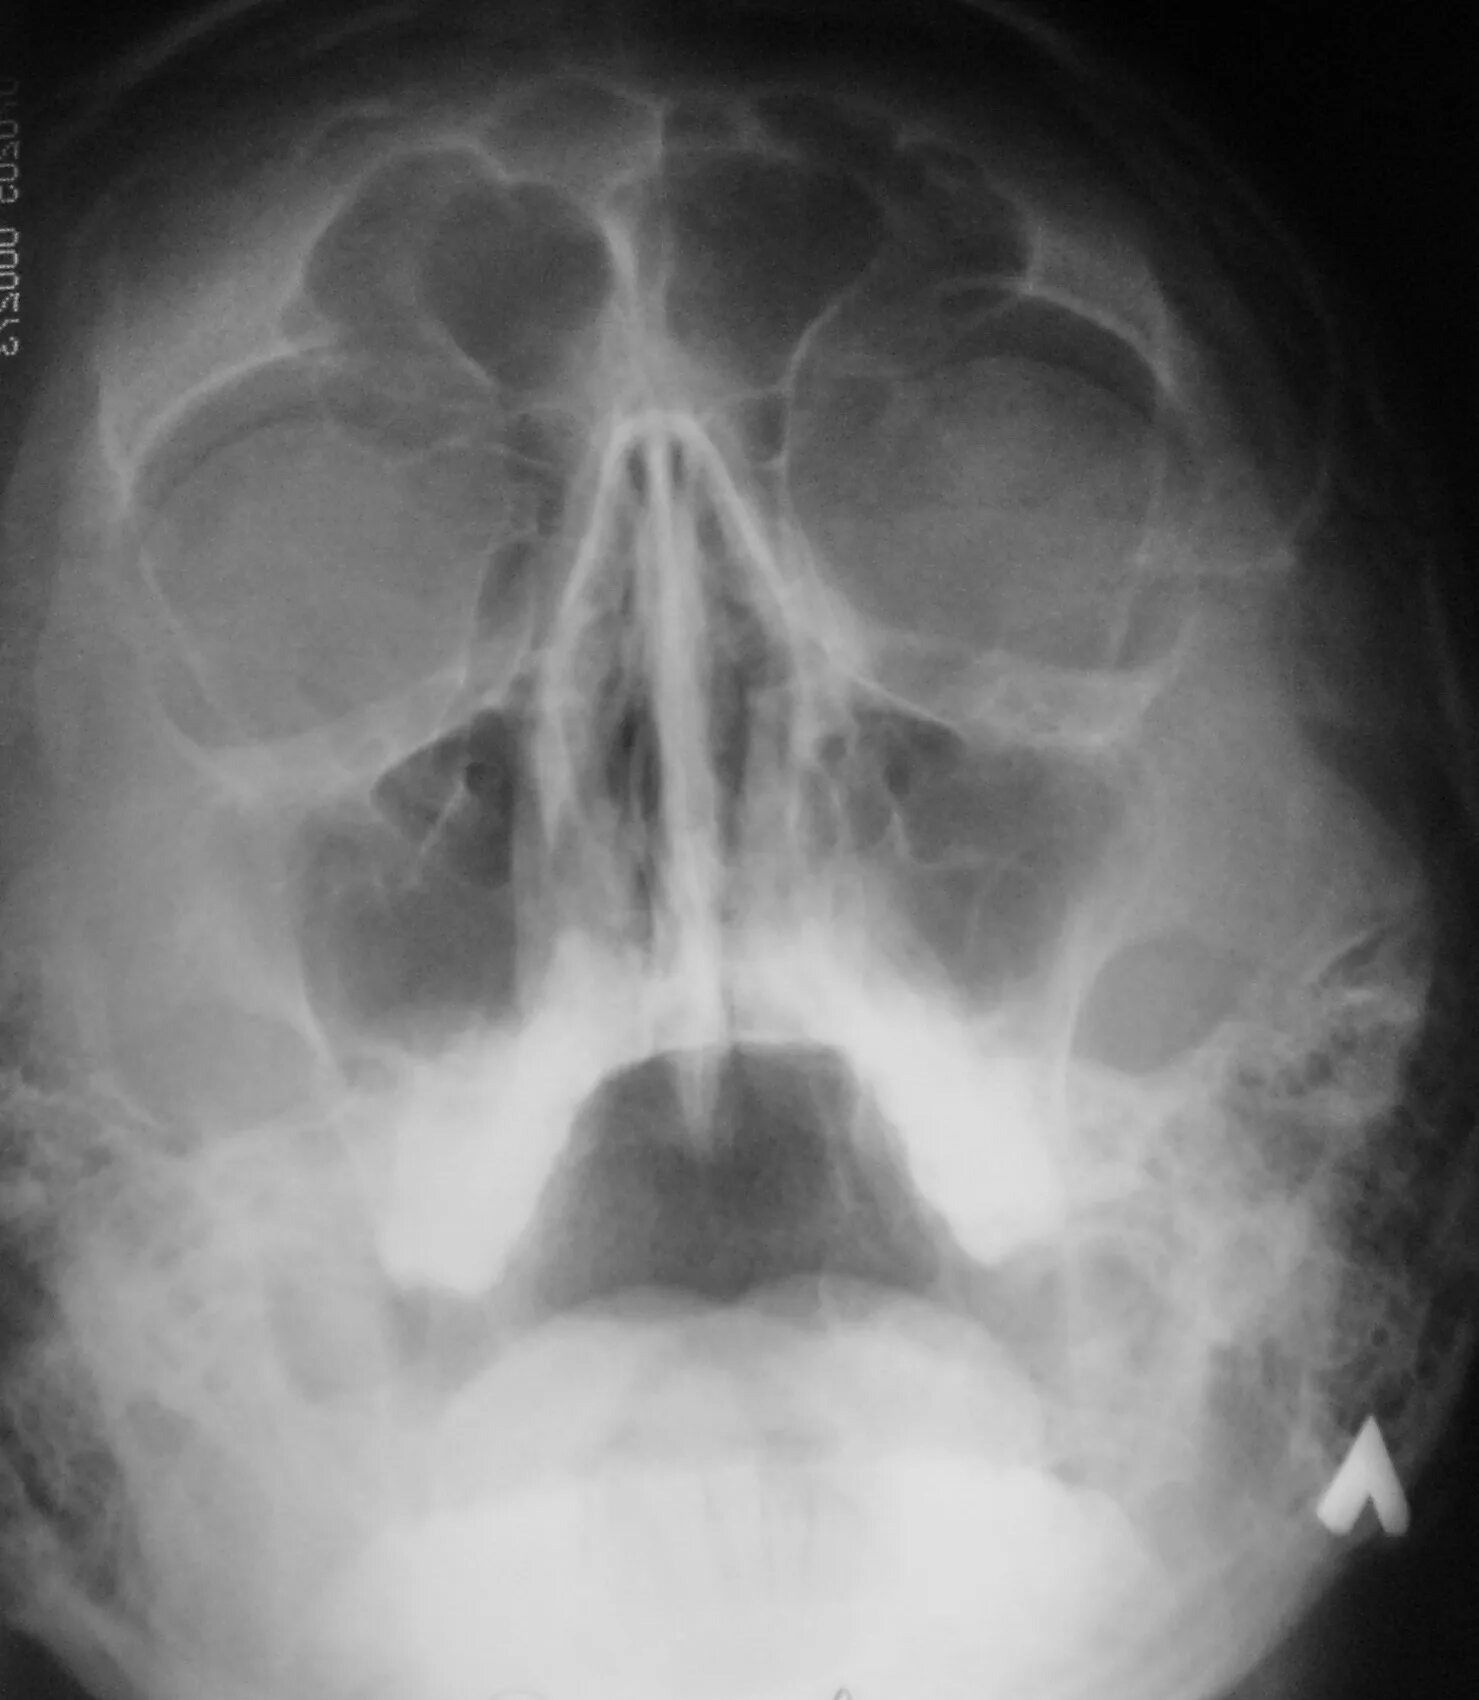

Как выглядит гайморит в носу